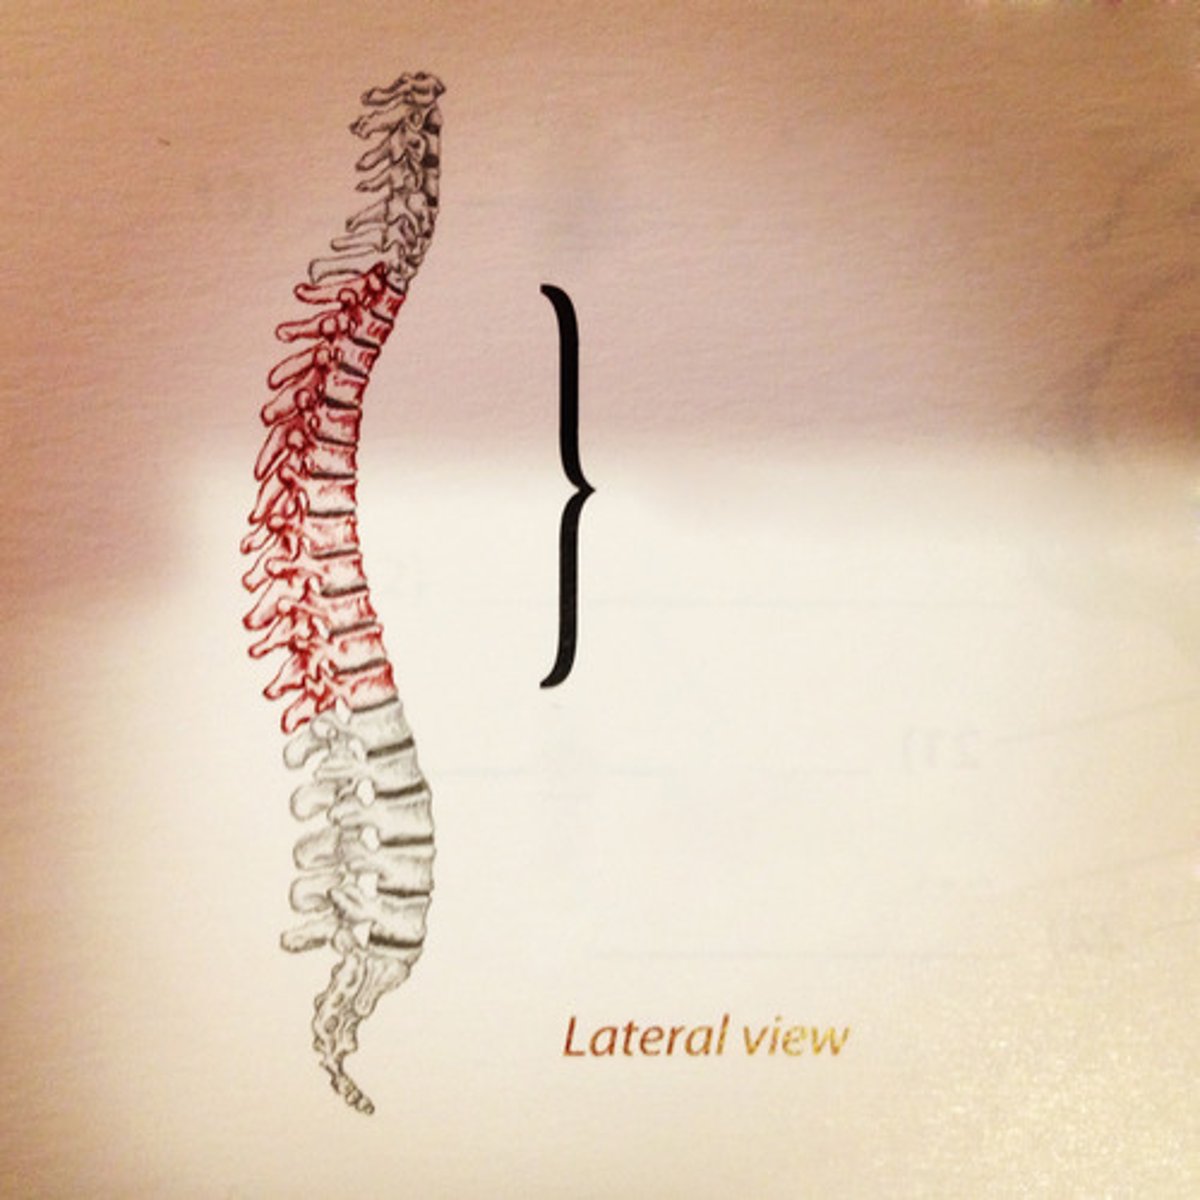

cervial lordosis (convex forwards)

thoracic kyphosis (convex backwards)

lumbar lordosis (convex forwards)

sacral kyphosis (convex backwards)